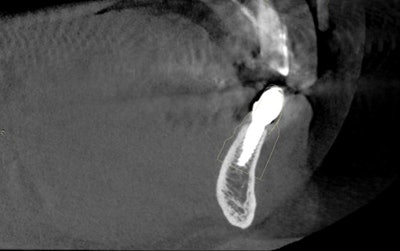

The natural progression when diagnosing in the third dimension is to enter the world of computer-assisted implantology and obtain a cone-beam CT (CBCT) scan for preimplant planning. Developing the surgical skills required to offer guided implant placement surgery will increase the success of your practice dramatically.

I use the Galileos 3D (Sirona) for an enhanced analysis with proper diagnosis, optimal treatment planning, and increased case acceptance. I know my success is fortified by my use of computer-assisted guided implantology.

Since the leading indication for obtaining a CBCT is preimplant planning, the natural evolution is to use this invaluable information to provide implant surgery and specifically guided implantology to our patients (figure 5). A greater level of safety is achieved and a higher standard of care that, in my opinion, is unmatched by conventional freehand implant surgery.

As you journey into implant placement with surgical guides, your level of confidence rises knowing you will precisely place your implant fixtures based on the 3D virtual plan devised in Galileos implant software. Placing realistic virtual implants into an edentulous site or multiple sites better prepares you for the actual placement (figure 6). I review any of the vital anatomical structures without distortions that might be encountered during surgery and make measurements that can be extremely advantageous when getting close to adjacent teeth, the incisive foramen, the mental foramen, the maxillary sinus, the mandibular canal, or an unusual mandibular concavity, to name a few.

The software provides us with safety margins to avoid penetrating these vital structures. You may find that a crestal sinus lift may be necessary to accept the planned fixture or that decreasing the length of the implant may be appropriate. Either way, you are not blindsided by atypical anatomy or underprepared for your procedure. This goes hand in hand with our "Do no harm" oath.